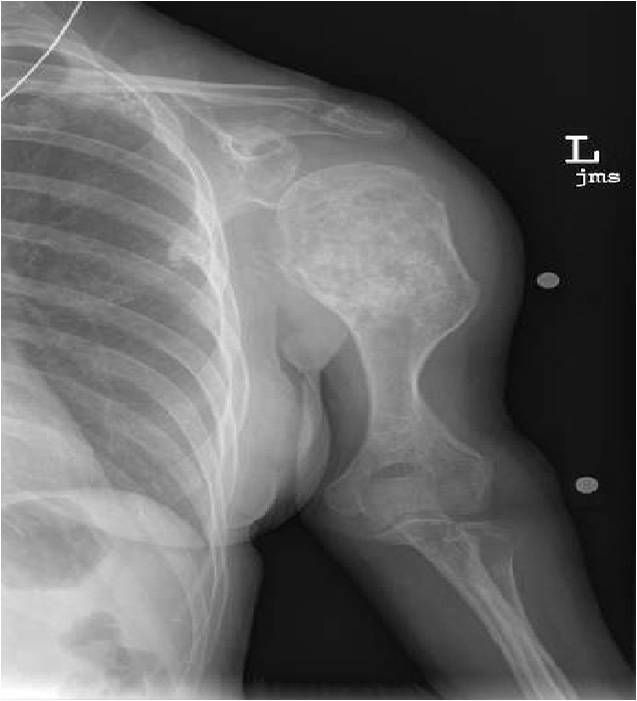

Ring and Arc Calcifications, Minimal Endosteal Scalloping, Cortex Intact, No Soft Tissue Component, No Periosteal Reaction

Minimal Endosteal Scalloping is Acceptable

Metaphyseal Tumor, Heavy Calcifications, Ring and Arc Pattern of Calcifications, Minimal Endosteal Scalloping, No Cortical Destruction, No Periosteal Reaction, No Cortical Destruction, No Soft Tissue Component

Metaphyseal Tumor, Heavy Calcifications, Ring and Arc Pattern of Calcifications, Minimal Endosteal Scalloping, No Cortical Destruction, No Periosteal Reaction, No Soft Tissue Component